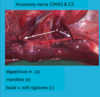

ligation of the Maxillary v.